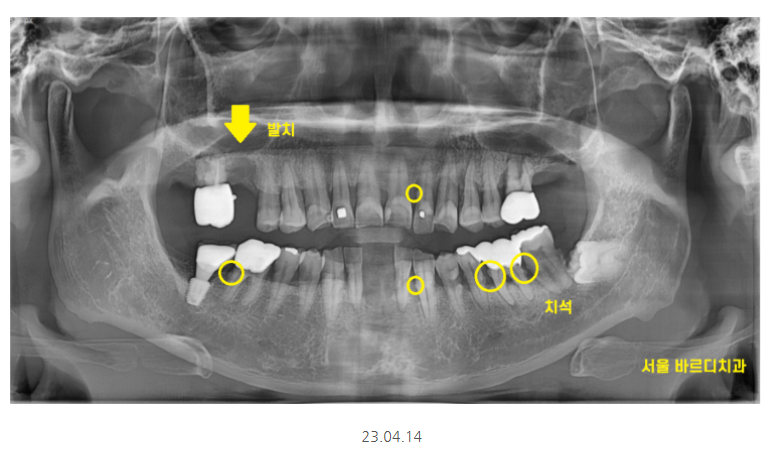

어금니 시림의 원인 치아가 파여서

충치가 있어서

잇몸이 안좋아서

다양한 원인이 있지만

해당 환자분은 잇몸이 안좋아서

이가 시리신거였습니다.

x-ray상에서 치석이 보일정도로

치석도 많고 잇몸관리가 안되고 계셨어요.

제일 불편을 호소한 치아 한개만 발치 후

임플란트를 진행했습니다.